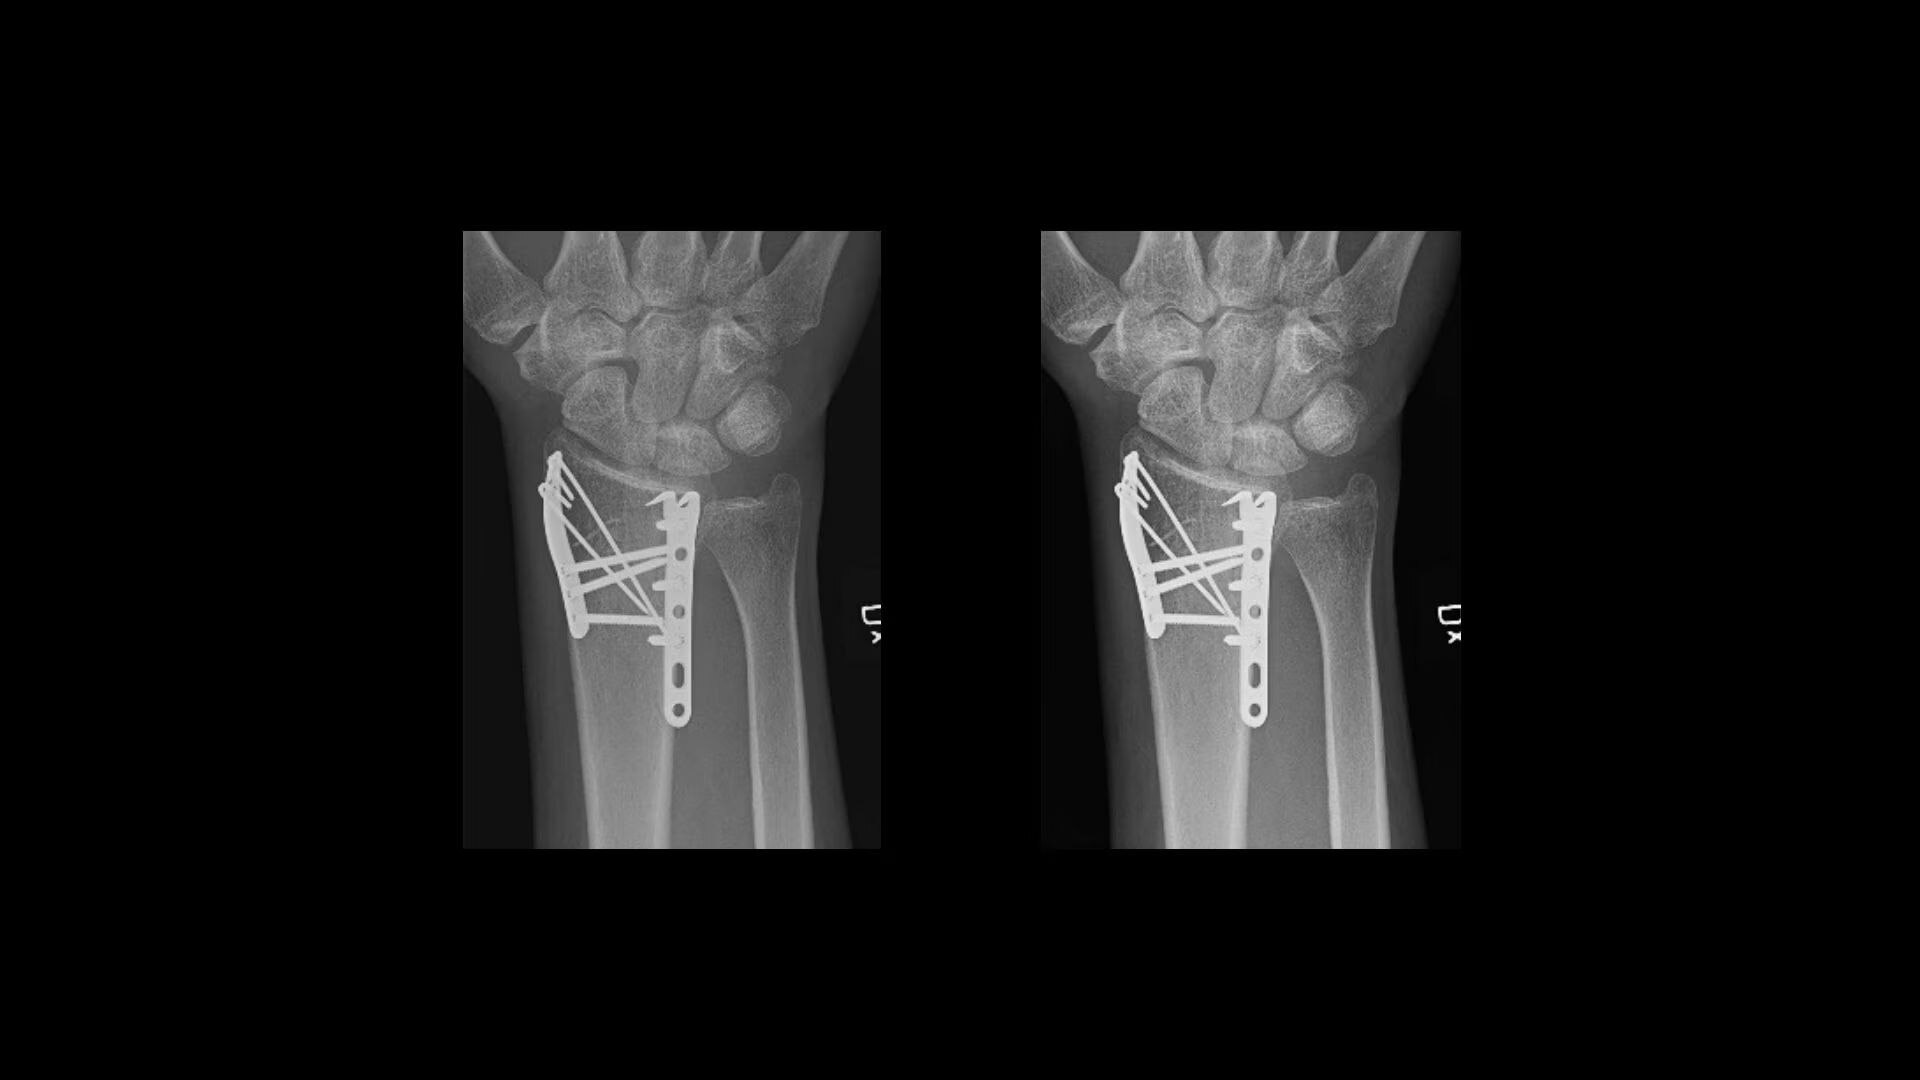

Metal implant handling

See clear bone-metal interface without halo artifact

Extraordinary anatomical detail at low dose

Helix™ Advanced Image Processing offers unparalleled sharpness, balanced contrast, and optimal brightness, even in the face of dose and patient anatomy variations, as well as challenging metal implants. Available on all of our fixed and mobile X-ray systems, Helix provides consistent performance regardless of exposure technique or exam conditions.